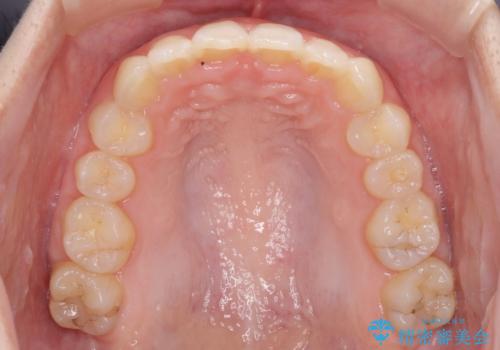

- 口元の深い咬み合わせ(ディープバイト)を気にして来院された患者様です。

インビザラインによる上下歯列の遠心移動(後方移動)により、口元のデコボコとディープバイトを改善することとしました。

下顎左右の犬歯とその後ろにある第一小臼歯、計4歯がシミュレーション通りに動かずディープバイトがなかなか改善されませんでした。

マウスピースの再製作を何度か行いましたがうまくいかないため、部分的にワイヤー矯正を併用することを提案しました。しかし、最も気になっていた前歯のデコボコはきれいに改善されたため、これ以上治療を希望されず、治療を終了することとしました。(今後気になった際には再開する予定です)